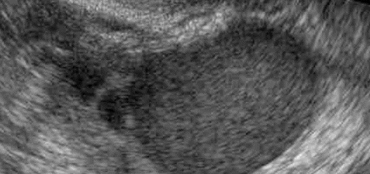

Obstétricale avec Doppler:

- 1er trimestre:

- Position: Allongée.

- Examen de datation et de dépistage des anomalies chromosomiques par la mesure de la clarté nucale.

- À vessie pleine par voie sus pubienne mais aussi par voie endovaginale si nécessaire.

- La période optimale pour la mesure de la clarté nucale est de 11 , 0 jour à 13 , 0 jour.